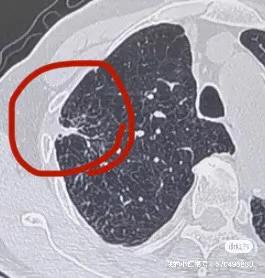

一個78歲合併冠狀動脈重度狹窄的冠心病病人,體檢發現右肺腫塊,由於不敢手術與常規穿刺活檢,在當地三甲醫院花了14800元做了血液基因檢測未發現相關驅動基因突變,準備做區域性放療,但又沒有病理診斷,最後多方打聽最終選擇一種國內特色的肺穿刺活檢技術——氬氦刀冷凍隧道式肺活檢專利技術。在局麻CT引導進行了冷凍活檢手術,活檢多條大塊組織標本,術中冰凍病理診斷是腺癌,即刻同期進行區域性完全性氬氦刀冷凍消融手術。其餘標本再次進行組織基因檢測,發現是EGFR21突變。後續直介面服奧希替尼靶向藥物治療,5個月後,腫瘤完全消失,腫大的縱隔淋巴結也恢復正常,臨床評估CR。本案例說明:1.對於不能手術、合併複雜基礎疾病或高齡的肺腫塊病人,這種特色是肺穿刺活檢技術(冷凍隧道活檢技術+穿刺標本現場冰凍病理診斷技術+同期冷凍消融技術)就是一種很好的選擇;2.對於腫瘤基因檢測,本案例顯示血液標本的準確性低於組織標本;3.對於腫瘤診療,只有精準診斷才有精準治療。